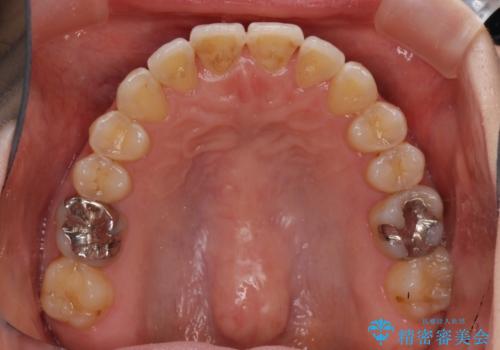

- 前歯のデコボコを治したいとのことで来院された患者様です。

上下顎ともに歯列全体の後方移動とIPR(歯と歯の間を削る)によってデコボコが解消するように設計し、インビザラインにより治療を行うこととしました。

1日22時間の装着時間をほとんど達成することができず、治療には当初予定の2倍以上の期間を要することとなりました。